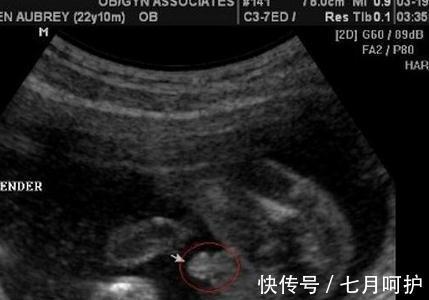

图像|B超看男女,最少只需要8周,开心一下下哦

1、一般情况下,通过看图像就能看到生男还是生女。我们在看B超单的时候,会看到B超的图像,如果发现图像比较长,就有可能是男孩,如果发现比较圆,就有可能是女孩。

12、b超单上除了胎囊大小,还有就是胎心率,胎心率超过150次/分的女宝多,低于150次/分的男宝多。